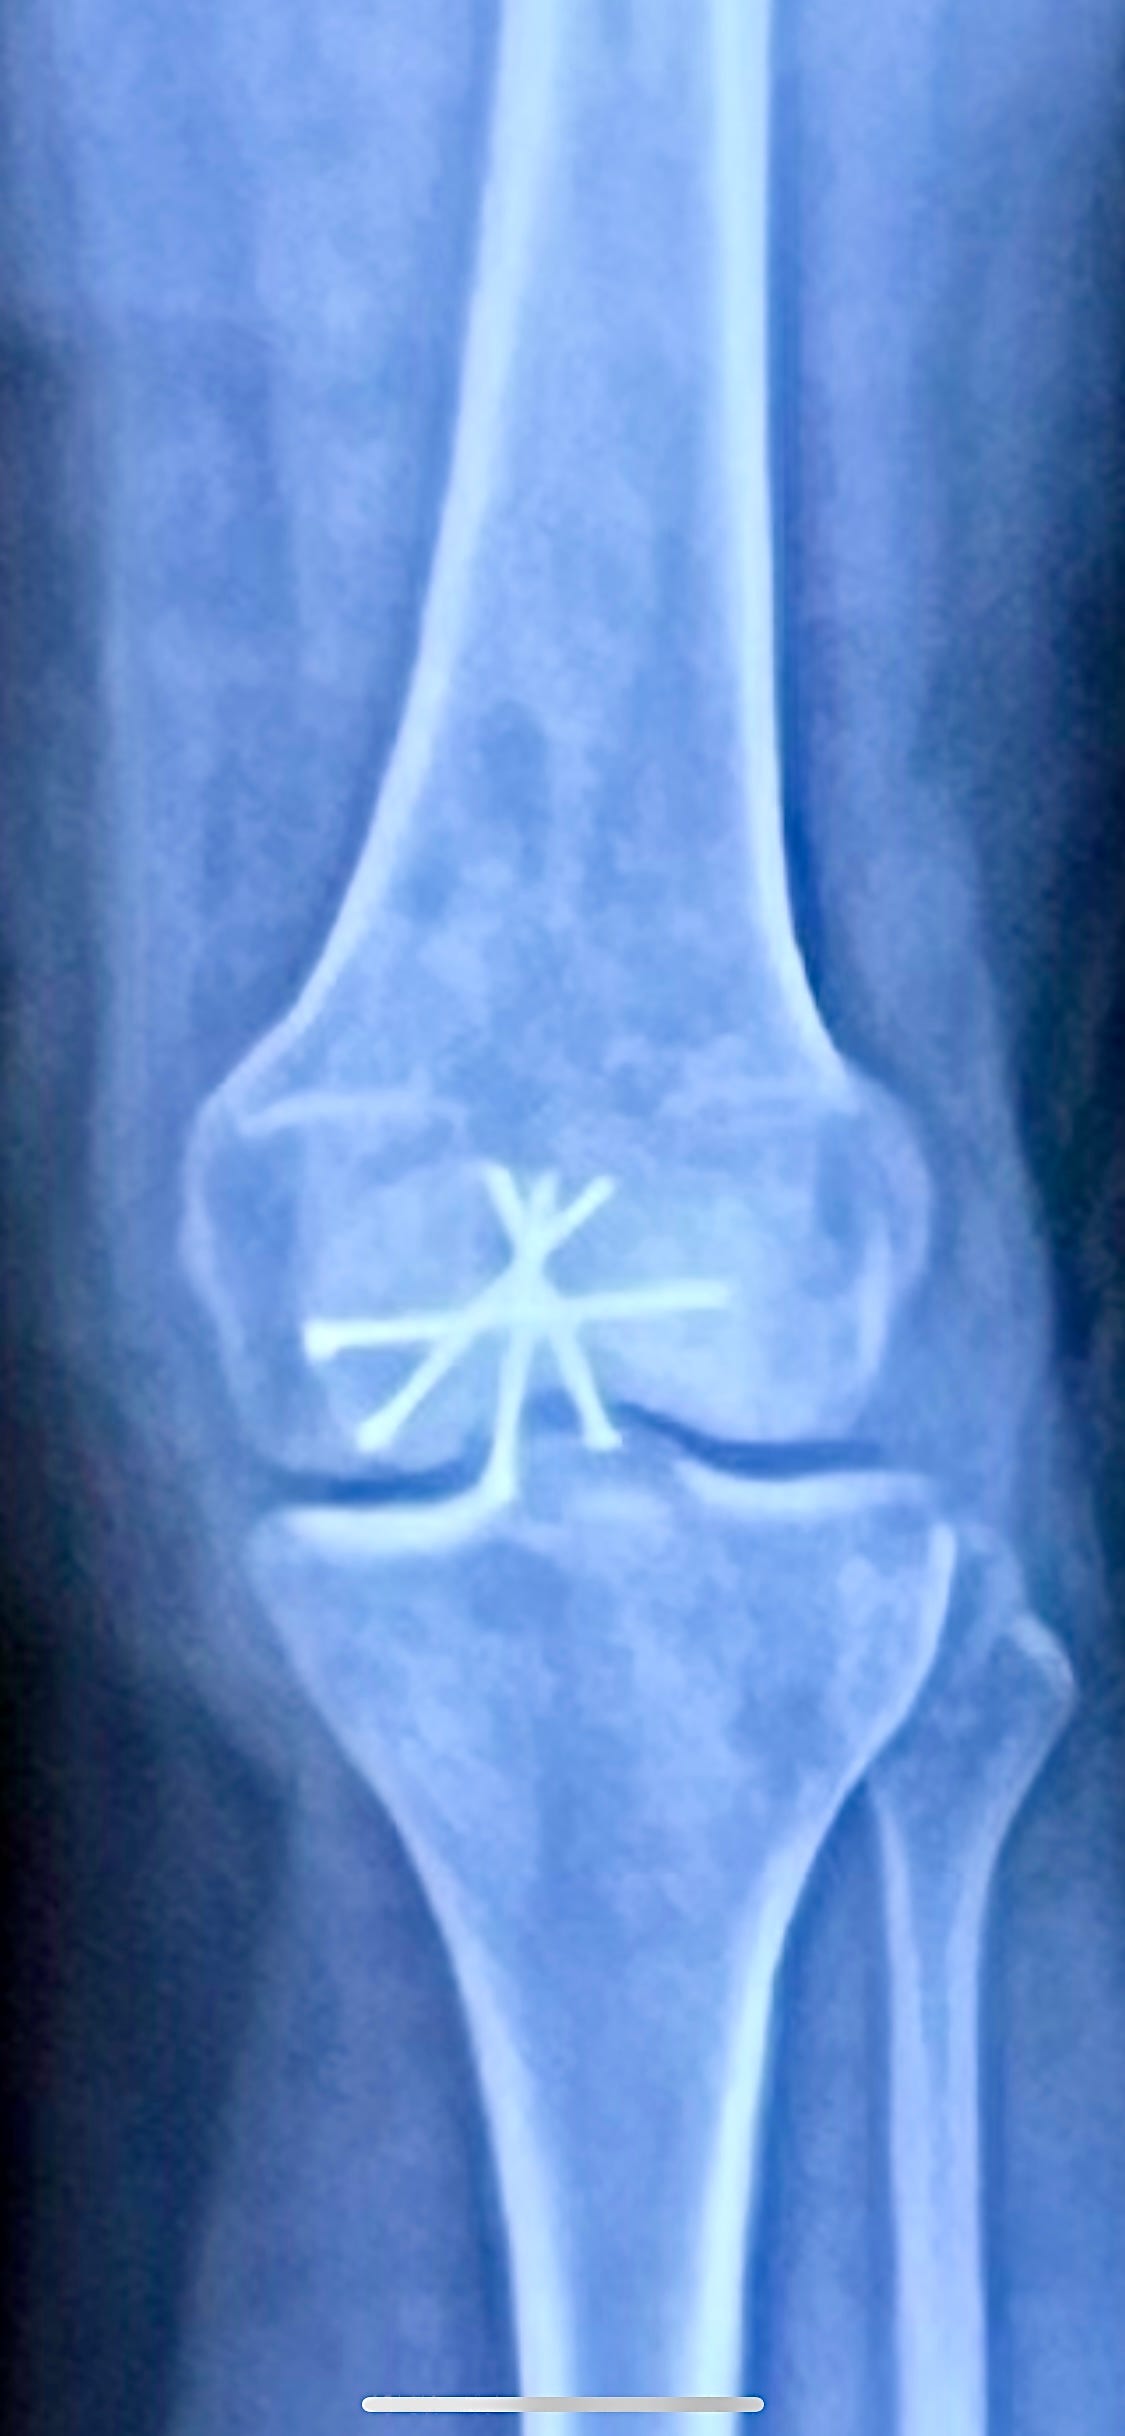

Almost three weeks ago, I slipped on a piece of celery in a grocery store and fell and shattered my kneecap into at least seven pieces. Some of the pieces were a full inch apart. “Of course, this sort of thing is usually a surgical issue,” the ER doctor told me after I’d ridden in an ambulance for the third time in my life, this time in hyperventilation-inducing pain. There was a surgery, and a fog of time, and there now lives in my patella a collection of rods and screws that form the shape of an asterisk, a star, a small burst of firework.

Recovery from a knee surgery is one of the most intense orthopedic surgery recovery processes. There is a time when you cannot bend the knee, when you Velcro it with great force into an immobilizer that holds it perfectly still. There is a time when you should bend the knee with help, but without engaging the quad, another human gently manipulating your limb as you relax it completely. There is a time when you must wear a new brace that holds the knee at a new angle, softening and strengthening your range of motion. There is a time when you test and retest the strength of the bone, when you reverse the atrophy of the quad, when you walk. This usually takes two months. In my case, the orthopedic team looks at the X-rays and the way the bones and sinews have been hashed, and tells me that time isn’t relevant here, don’t count, it will be many, many months. I am still not allowed to move the knee.